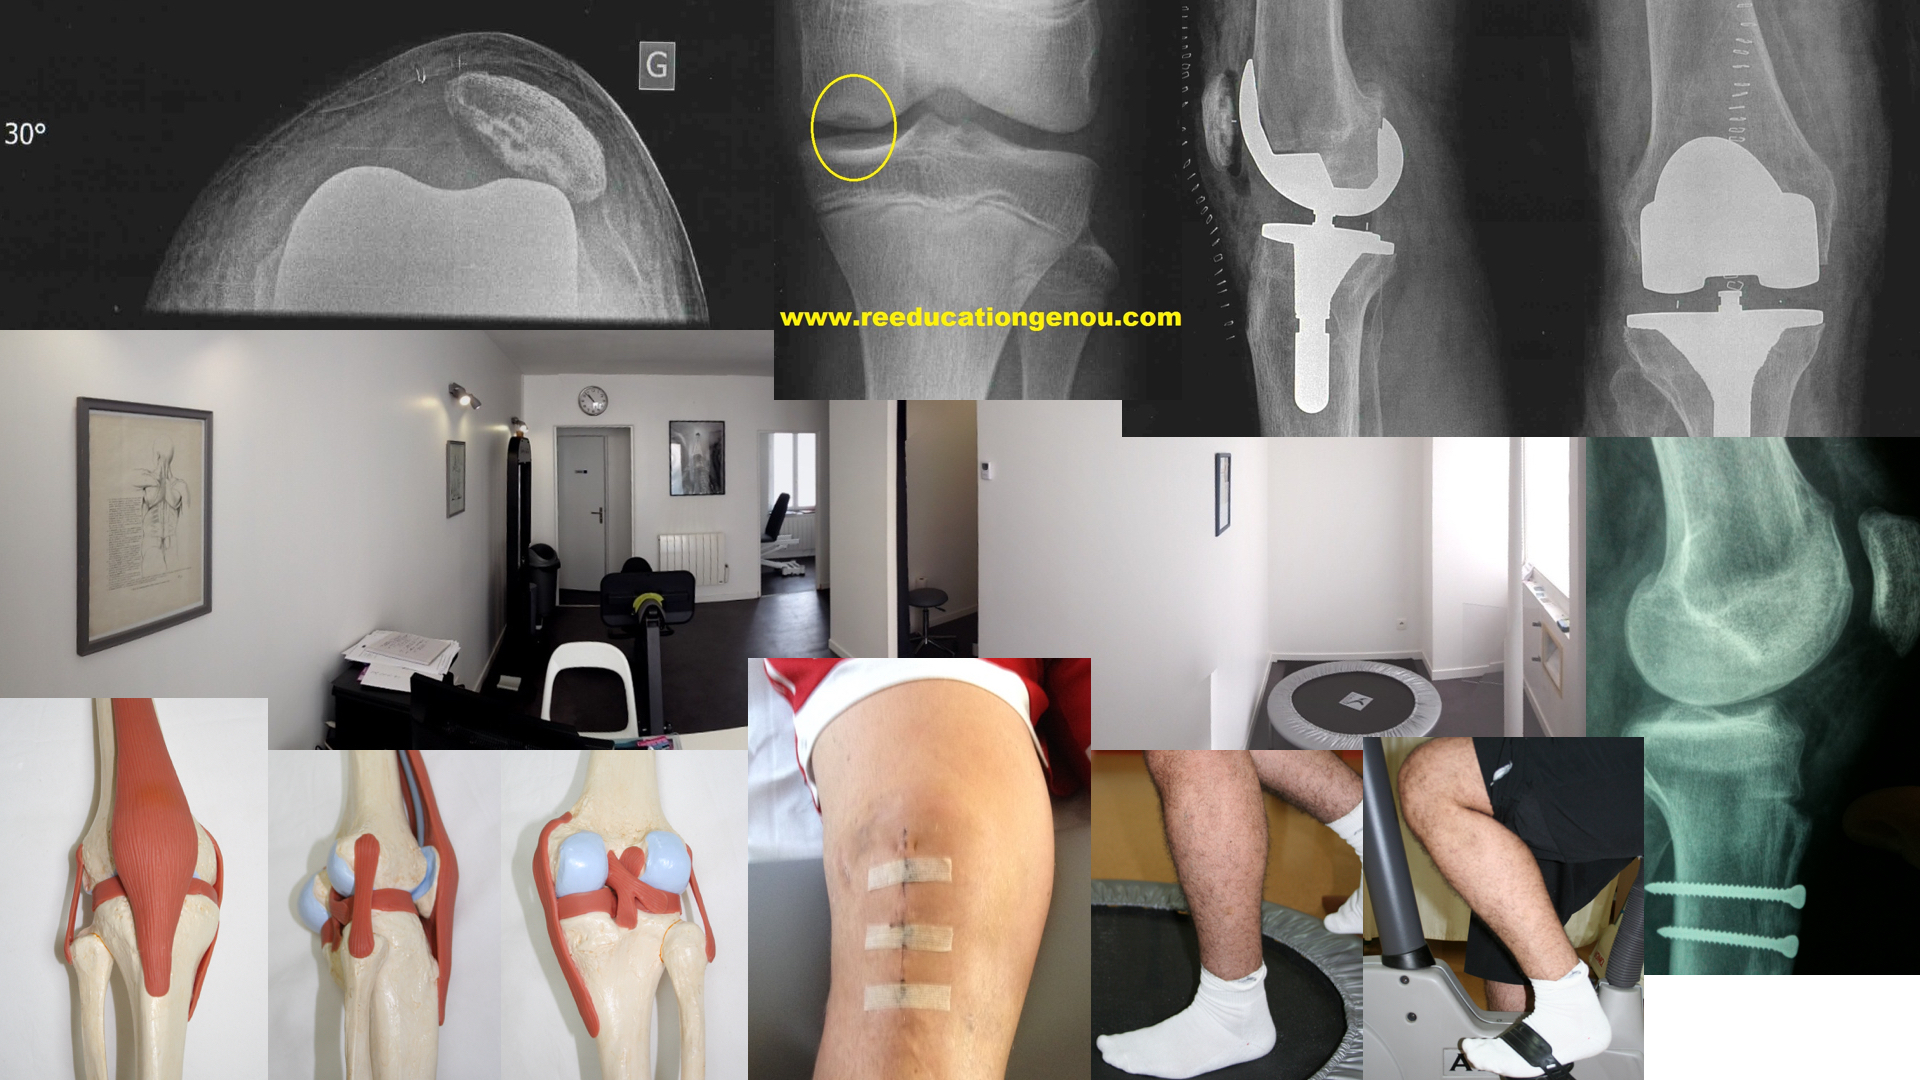

Arthroscopie, méniscectomie, suture méniscale

Les ménisques sont l'amortisseur entre le fémur et le tibia.

Le ménisque interne ou médial est en forme de C, le latéral ou externe est en forme de O presque fermé.

Le ménisque est un fibrocartilage

Les ménisques sont un supplément de (fibro)cartilage important dont le rôle de glissement est essentiel.

Le mouvement des ménisques des étroitement lié aux mouvement des condyles du fémur. Lors de la flexion le ménisque latéral recule d'un centimètre alors que le médial ne recule que d'un demi centimètre.

Le retour vers l'extension augmente le rayon de courbure du ménisque, la flexion diminue le rayon de courbure.

Sans ménisque l'usure du cartilage est très accélérée. De même une opération du ménisque changera la capacité méniscale à amotir et donc protéger le cartilage.

Ils sont stabilisateurs de l'articulation par leur forme en coupole retenant par le bas le femur lors des flexions et extensions du genou et c'est pour cela qu'une lésion du ménisque a des conséquences sur la mécanique à long terme de l'articulation du genou. De même qu'une atteinte du ligament croisé antérieur va mécaniser et user plus rapidement le ménisque interne.

L'anse de seau : c'est une fissure verticale s'étendant de l'arrière (corne postérieure) vers l'avant (corne antérieure), cela détache une bandelette qui est luxée entre les deux condyles = l'échancrure. cela produit un blocage méniscal irréductible ou non autour de 30-40 degrés de flexion. La fissure horizontale elle produit plutot des kystes poplité.

Le chirurgien différencie 3 zones quand il observe un ménisque

• une zone dite "rouge-rouge" qui est la plus périphérique, la plus pentue et la plus stabilisatrice des mouvements du femur. cette zone a une capacité de cicatrisation car elle est en contact avec une vascularisation via la capsule articulaire (d'où le terme "rouge"). Après 50 ans seul le quart le plus en contact avec la capsule est vascularisé. Cette zone peut être suturée si besoin et surtout chez le jeune.

• Une zone intermédiaire dite "rouge-blanche" qui est moins cicatrisable car moins vascularisée. cette zone est rarement suturée car elle cicatrise moins.

• et une zone proche du milieu du genou qui est dite "blanche-blanche" et donc non cicatrisable...c'est la zone qui en général est retirée lors d'une arthroscopie (houla je simplifie beaucoup là)

coupe d'un ménisque et sa vascularisation (source Maitrise orthop. Ph Beaufils)